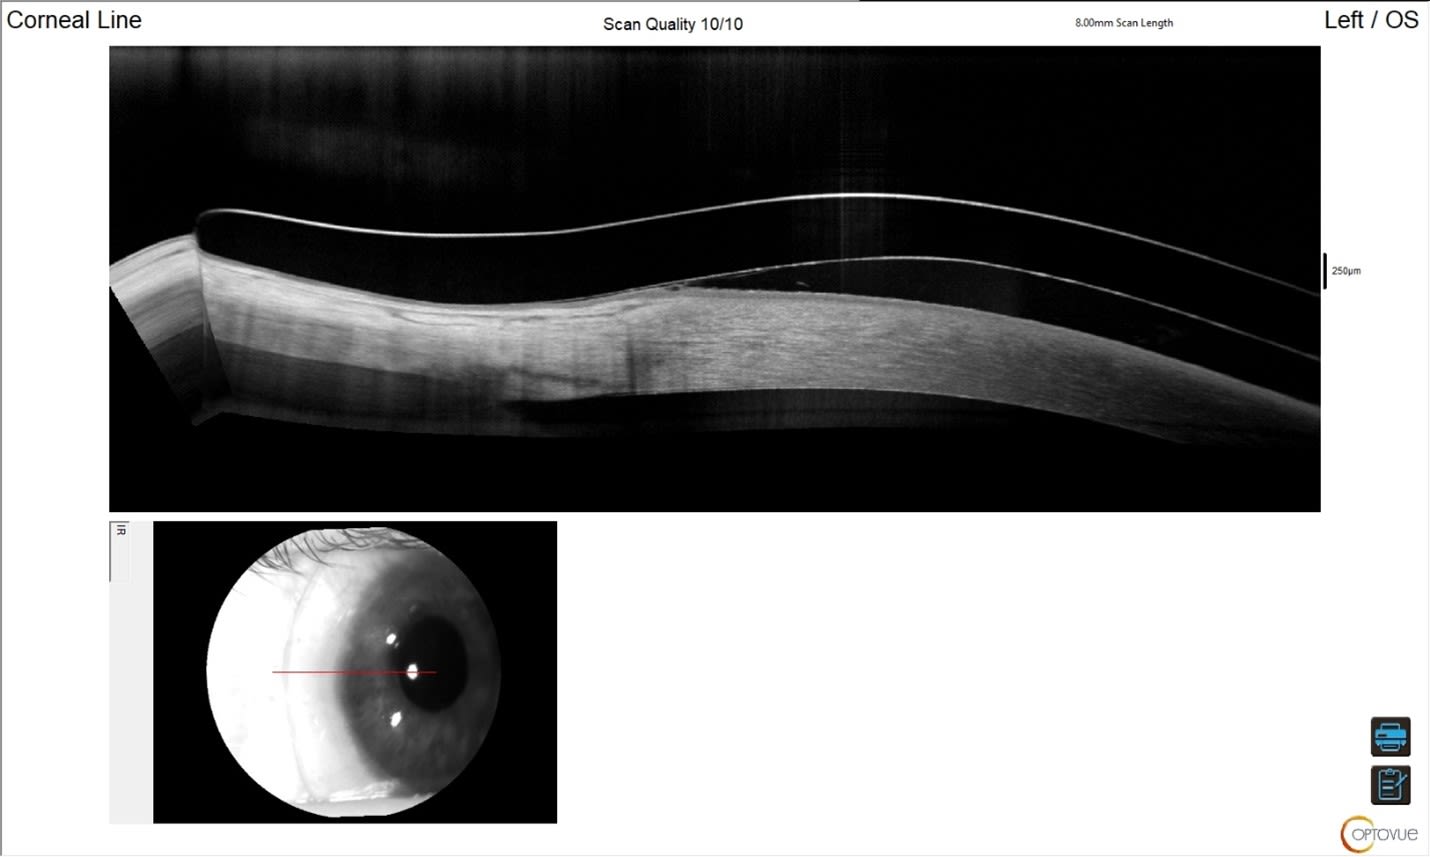

At dispense, AL’s vision was 20/20+2 OS. The anterior segment OCTs are shown below (Figures 2 through 6). We imaged scleral prosthetic lenses centrally and in four principal meridians at the haptics to ensure an optimal fit.